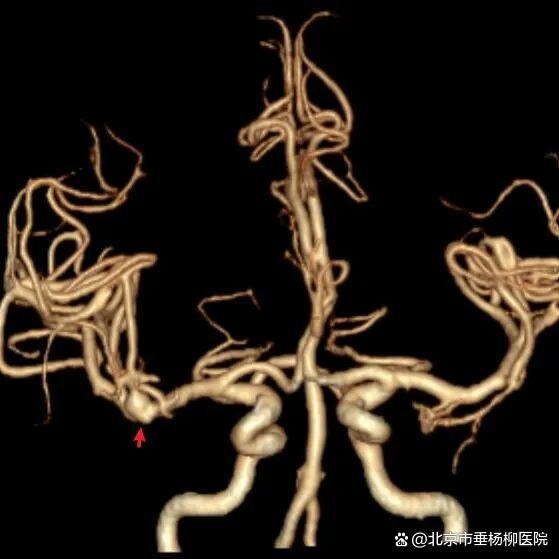

病例一为77岁女性患者,既往高血压病史。因“突发剧烈头痛伴恶心2天”前来清华大学附属垂杨柳医院急诊科就诊。头颅CT检查提示蛛网膜下腔出血,头颈动脉CTA提示右侧大脑中动脉M1段分叉处宽颈动脉瘤。神经外科脑血管病介入团队急诊为患者实施了全脑血管造影术(DSA),造影显示动脉瘤不规则,可见子囊,宽颈,主要累及下干。团队采取了支架辅助弹簧圈栓塞术,患者颅内“不定时炸弹”被成功拆除。动脉瘤达到致密栓塞,载瘤动脉通畅。住院半个月后顺利出院,无神经功能障碍。

▲CTA显示右侧大脑中动脉分叉动脉瘤